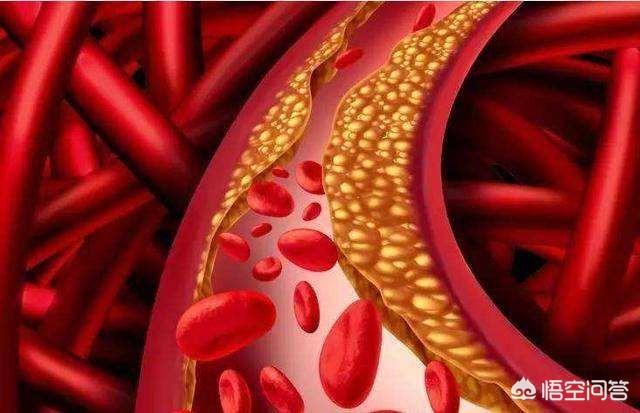

Sous l'influence de facteurs de risque cardiovasculaire tels que l'hyperlipidémie, la paroi interne des vaisseaux sanguins est progressivement endommagée et les lipides en excès dans le sang se déposent progressivement sous la paroi du vaisseau, formant un noyau lipidique athéromateux jaune, et finalement une chape fibreuse se forme dans le noyau lipidique, ce qui constitue le processus de formation de la plaque artérielle. La plaque est un facteur de risque conduisant à l'athérosclérose, et les plaques qui ont des problèmes de stabilité et se rompent peuvent conduire à une agrégation plaquettaire réactive. L'agrégation réactive des plaquettes peut même conduire à la formation de caillots sanguins, bloquant les vaisseaux artériels et provoquant des maladies cardiovasculaires infarciques. Ce qu'il faut faire, c'est prévenir la formation de la plaque par des médicaments et des exercices raisonnables, essayer de maintenir la stabilité de la plaque existante, ralentir le processus d'athérosclérose et empêcher la rupture de la plaque d'entraîner un risque plus élevé.

La formation de la plaque est un long processus qui se produit progressivement lorsque l'excès de lipides dans l'organisme s'accumule sur les parois des vaisseaux sanguins. Une fois la plaque formée, il est très difficile de la faire disparaître. En fait, presque toutes les personnes âgées ont des plaques, mais toutes les plaques ne conduisent pas à des maladies cardiovasculaires et cérébrovasculaires. Les plaques instables sont plus dangereuses et se rompent, mais les plaques stables sont généralement inoffensives tant que l'on veille à contrôler leur croissance continue et qu'elles n'entraînent pas de rétrécissement grave des vaisseaux sanguins. Il convient de noter que les plaques instables peuvent se rompre sous l'effet de certains facteurs déclenchants défavorables, tandis que les plaques stables peuvent continuer à croître ou devenir vulnérables. Par conséquent, la seule chose que nous puissions faire est d'essayer de stabiliser la plaque et de ralentir sa croissance afin d'éviter des conséquences graves. L'exercice physique est une intervention sur le mode de vie et les médicaments sont un traitement pharmacologique. Pour les personnes qui forment des plaques, l'un ou l'autre est indispensable à la prévention des maladies cardiovasculaires et cérébrovasculaires. Cependant, même les médicaments associés à des interventions sur le mode de vie ne permettent pas d'obtenir une régression complète de la plaque.

La plaque a la plaque veineuse, la plaque artérielle, c'est dans le rôle de multiples facteurs étiologiques, en raison de la lipidation de la précipitation, pour dire les choses franchement, c'est-à-dire, vous graissez plus, la digestion et l'utilisation ne peut pas être, dans les lipides sanguins quatre et d'autres facteurs multiples sous l'influence de et puis des dommages à l'intima, le dépôt à la couche interne des vaisseaux sanguins, la formation d'un noyau lipidique jaune athéromateux, et finalement dans la formation d'un noyau fibreux sur le noyau lipidique, qui est normalement très stable, si la coiffe fibreuse est soumise à une inflammation soutenue. la chape fibreuse se rompt, la plaque s'écoule et les plaquettes sanguines dans le mariage éclair donnent naissance à un enfant perturbateur, appelé thrombus, qui se promène pour semer le trouble, se spécialise dans les mauvaises actions pour bloquer les vaisseaux sanguins, le thrombus dans la lumière des vaisseaux sanguins devient plus étroit en même temps, mais aussi se rompt, déclenchant des événements vasculaires cardio-cérébraux et cérébraux aigus, tels que l'accident vasculaire cérébral, l'infarctus du myocarde, l'embolie pulmonaire, l'insuffisance rénale, les veines variqueuses, etc. etc. Par conséquent, l'élimination de la plaque ne permet pas seulement de déboucher les vaisseaux sanguins, mais aussi de prévenir les accidents cardiovasculaires et cérébrovasculaires aigus, ce qui est dans l'esprit de tout le monde.

L'athérosclérose est une lésion endothéliale des vaisseaux sanguins artériels dont souffre tout adulte, même à partir de l'adolescence. Elle se développe lentement au fil des décennies et finit par former des plaques d'athérome qui obstruent les vaisseaux sanguins ou provoquent leur rupture, entraînant de graves maladies cardiovasculaires et cérébrovasculaires, telles que l'hémorragie cérébrale, l'infarctus cérébral, la maladie coronarienne et la séparation de la coarctation aortique.

Le processus de formation de la plaque passe par plusieurs étapes : tout d'abord, l'endothélium du vaisseau sanguin est endommagé, comme si la couche protectrice de la surface interne du vaisseau sanguin était "brisée" ; les macromolécules de graisses présentes dans le sang sont transportées par une sorte de substance appelée lipoprotéine de basse densité dans la couche intima-média de la paroi du vaisseau sanguin, où elles s'accumulent en grandes quantités ; la paroi du vaisseau sanguin s'épaissit et le traitement médical consiste à épaissir la couche intima-média de plus d'un millimètre, ce qui est considéré comme de l'athérosclérose. Lorsque l'épaississement de la couche intima-média dépasse 1 mm, on parle d'athérosclérose, telle que l'agrégation locale en une masse, c'est-à-dire la plaque précoce.

Au début de la formation de la plaque, l'accumulation de graisse provoque une série de réactions inflammatoires ; en fait, la graisse est constamment oxydée, dénaturée et forme des substances ressemblant à de la bouillie ; ces substances détruisent la structure normale des vaisseaux sanguins et deviennent partie intégrante des vaisseaux sanguins ; à ce moment-là, la matière lipidique est principalement à l'état liquide, ce que l'on appelle généralement des taches molles.